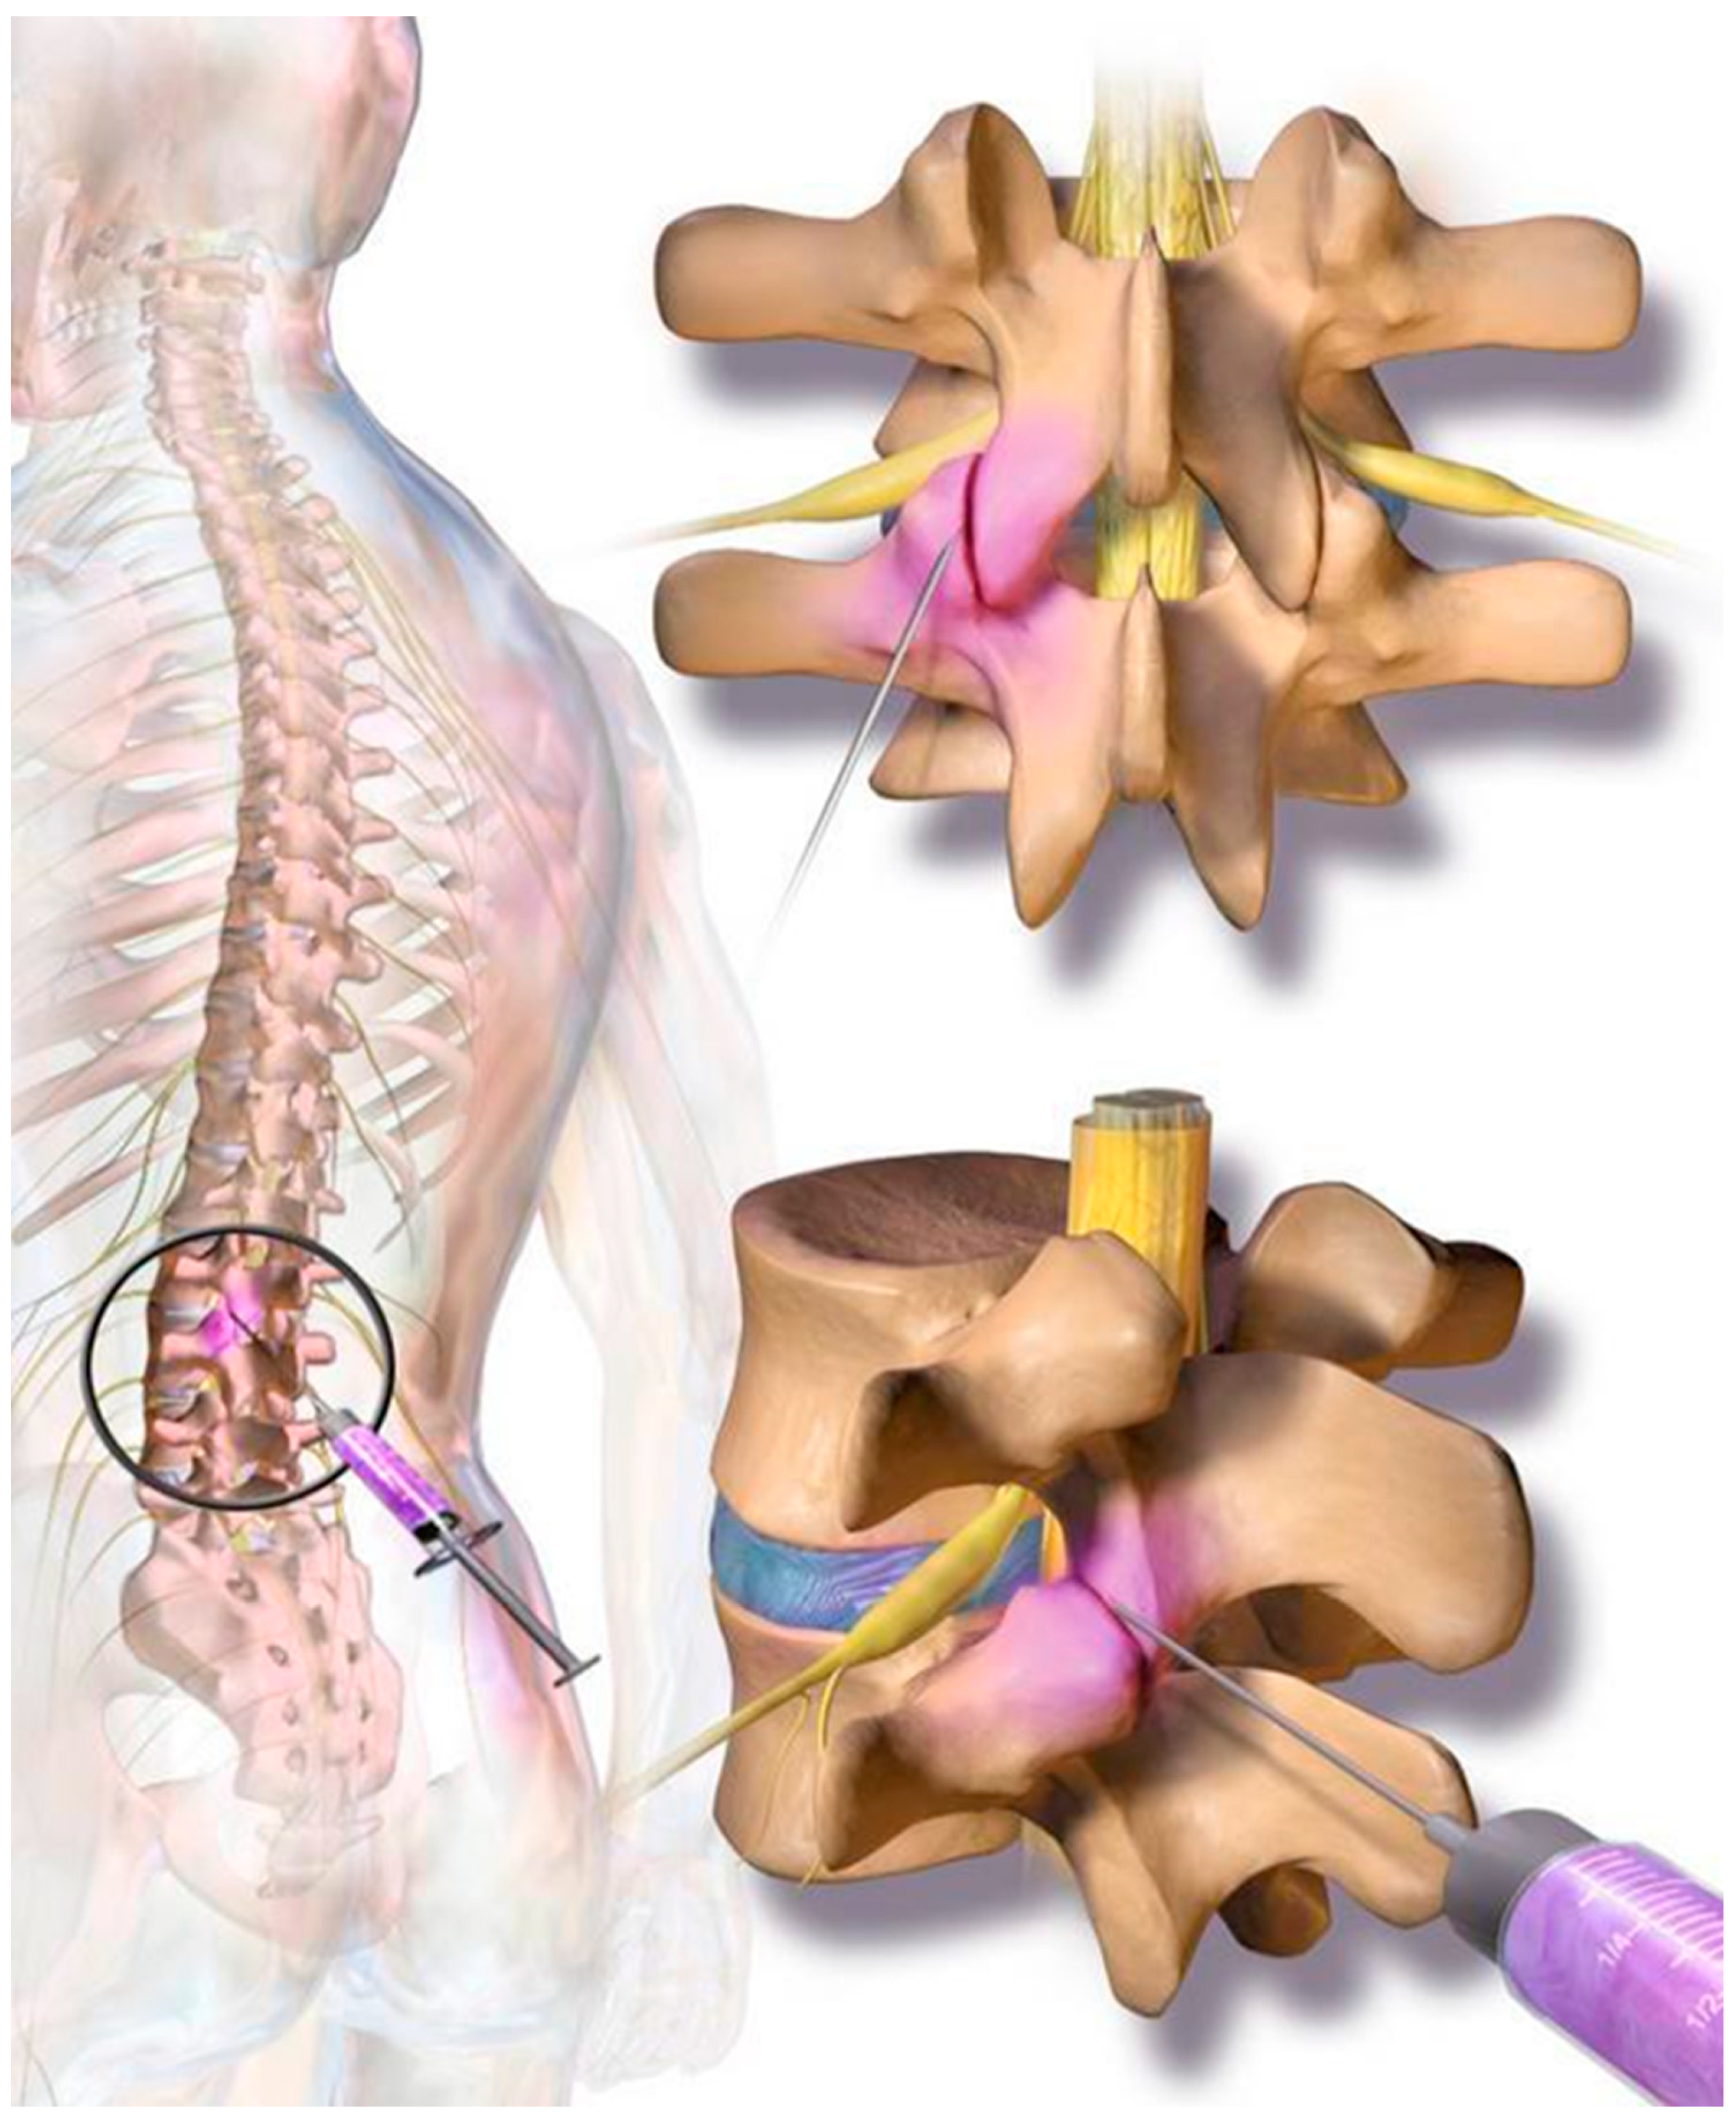

Low back pain (LBP) poses an economic burden to society, mainly in terms of the large number of workdays lost by a small percentage of patients who develop chronic forms of low back pain. A whole variety of pathological processes are responsible for low back pain. One of the leading anatomical structures involved in the pathogenesis of low back pain are the facet joints. Lumbar spinal facet joints were first suggested in the medical literature as a source of low back and lower extremity pain in 1941 [1]. Since then, the so-called “facetogenic back pain” has become a widely accepted diagnosis, though still controversial in the literature [2,3,4,5,6,7,8]. The most substantial support comes from investigations reporting successful back pain relief following peri-articular joint injections [9,10]. Estimates of lumbar facet joint pain prevalence based on single diagnostic blocks have ranged from 7.7% to 75% among patients reporting back pain [11]. The facet joint syndrome is a degenerative process of the facet joint’s cartilage following degeneration of an intervertebral disc that leads to height loss of the segment, resulting in a mechanically induced overload and arthrosis of the respective facet joints (Figure 1). These small joints are made for flexibility but not for weight bearing. Mechanically induced chronic weight overload finally results in a chronic inflammatory process involving the immune system, producing local inflammatory reactions with the synthesis of several pro-inflammatory cytokines and metalloproteinases [12]. Due to the inflammatory nature of the disease, local injection of glucocorticoids into the affected joint has become a standard treatment option. However, several studies suggest that such injections represent no long-term treatment for patients with chronic back pain [13]. Regenerative cell therapy, which refers to the therapeutic application of stem cells to repair diseased or injured tissue, has received increasing attention from basic scientists, clinicians, and the public. Stem cells hold significant promise for tissue regeneration due to their innate ability to provide a renewable supply of cells that can form multiple cell types, whole tissue structures, and even organs. Stem cells are present in the human body at all stages of life from the earliest times of an embryo through adulthood and senescence. Recently, it could be shown that interactions of human bone marrow-derived stem cells (MSCs) can limit and mitigate the inflammatory responses in the peri-articular fat by promoting anti-inflammatory pathways [14]. Bone marrow-derived MSCs are harvested by puncture of the iliac crest. This procedure is likely accompanied by some risks to the patient, such as long-term damage to the regenerative hematopoietic potential of the bone marrow, after the removal of hundreds of millions of valuable bone marrow cells. About 99% of the cells removed are hematopoietic progenitors, less suitable for tissue renewal outside the hematopoietic system. It seems inefficient to recover a small number of actual pluripotent stem cells to damage the pool of valuable bone marrow cells primarily as it is known that the number of vital bone marrow cells declines with increasing age. A key function of stem cells in the adult body is to contribute to the homeostasis of tissue resident parenchymal cells. As we age, there is a continuous turnover in almost every tissue between dying and replacing cells with the exception of some nerve cells in the brain. For a long time, our body can maintain tissue homeostasis. However, tissue homeostasis can be disturbed with increasing age in all tissues, such as tendons, bone, joints, heart, liver, kidneys, and muscles, in a way that the parenchymal cells, which are responsible for the organ function, are more frequently replaced by mesenchymal fibroblastic cells. This is due to a lack of renewing power, especially if ischemia, infections, accidents, and other inflammatory or traumatic events accelerate the tissue turnover. A good example is chronic wounds that show a number of problems, including insufficient levels of cell proliferation, increased cell senescence/apoptosis, impaired angiogenesis/neovascularization, inflammation, increased production of matrix metalloproteinases (MMPs), increased matrix degradation, and decreased production of extracellular matrix. Stem cell therapy is to be considered as the principal of transferring concentrated stem cells, which have been taken from one part of the body where they are not ‘missed’, to tissue in need of regeneration, in order to re-establish tissue homeostasis. The isolation of stem cells from suitable tissue (such as adipose tissue) and their application to other injured tissue and organs can be interpreted as the most gentle and natural approach to help the body in self-repair by increasing the number of stem cells at a location where they are exhausted but most needed. From these considerations, it also becomes clear that stem cell therapy is not only directed to a specific organ, tissue, or disease, but it will take the function of replacing and repairing tissue and organs that suffer from a lack of repair, renewal, and rejuvenation [15,16].

Figure 1.

On each level at the back of the spine, two small facet (zygapophyseal) joints—one from an upper and one from a lower vertebra—act as connectors to the spine and provide support as they allow the spine to bend and move. Facet joint syndrome significantly contributes to the high prevalence of back pain observed in western societies. Current therapies include local cortisone injections; however, there are mixed and negative reports regarding long-term efficacy for facet joint syndrome pain relief.